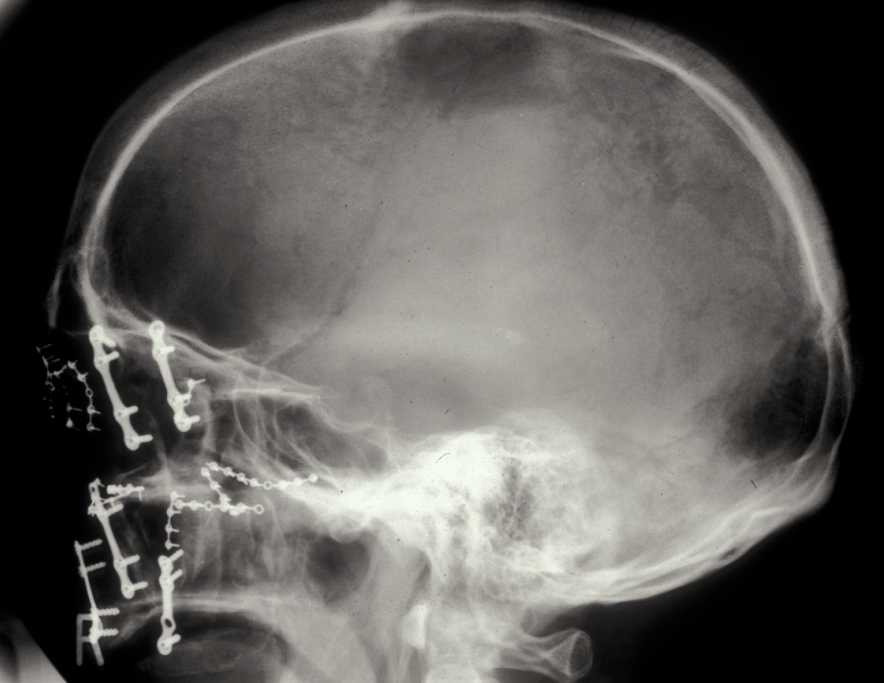

In the region of the angle of the mandible, a single plate is adequate to allow healing. In practice many surgeons now supplement this (or even replace it) with a transbuccally placed lateral plate which prevents lateral displacement of the lower border of the mandible. All these techniques use monocortically placed matching titanium screws to retain the plates which immobilise the fracture sites. Long-acting local anaesthetic regional block provides good postoperative analgesia and prophylactic broad-spectrum antibiotics are given preoperatively. Intraoral wounds are closed with resorbable sutures. If the occlusion is fully restored and stability of the fracture is assured by the plates, the intermaxillary fixation can be removed. Postoperative radiographs are taken to ensure correct placement of plates and screws and accurate realignment of mandibular fragments. It is also important to reassess the position of the condyles following ORIF as malpositioning can lead to TMJ problems later on (see Figure 5).